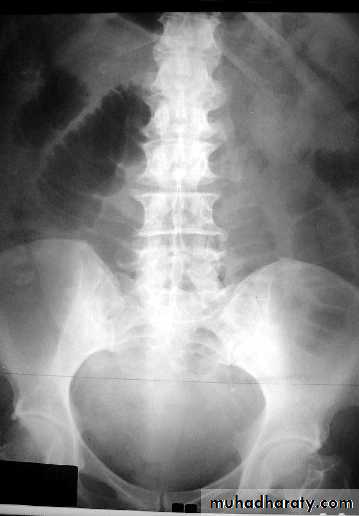

• Signs of low atresia :

• 1- Multiple air fluid level due to obstruction .

• 2- In AP view the distance between the terminal rectal segment and the marker should not exceed 2 cm.

• 3- In lateral view the terminal air shadow is seen above the pubo-coccygeal line.

• Signs of high atresia

• 1- In AP view the distance more than 2 cm .• 2-In lateral view the terminal air is below the pubo-coccygeal line .

Low type

High type